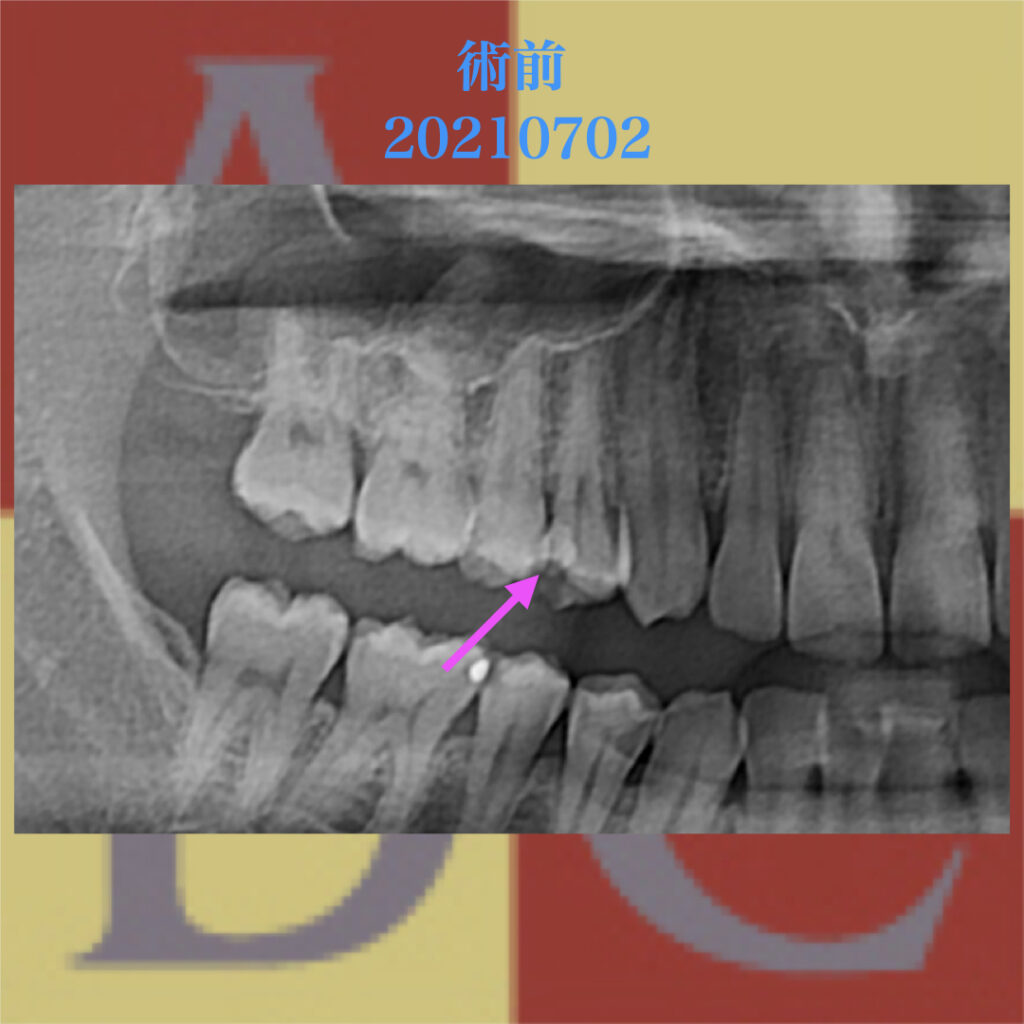

他院で抜歯宣告・・・から歯の保存:歯根端切除術

歯根端切除術

根尖性歯周炎・歯根嚢胞